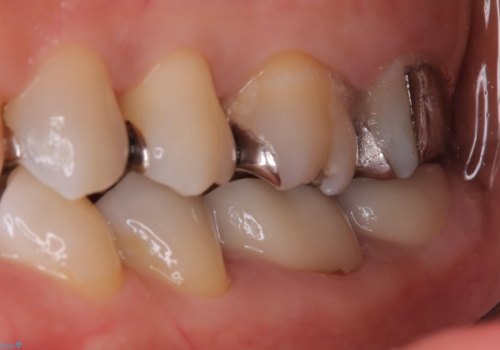

保険適用のメタルインレーと歯質の境目にう窩ができており、補綴物のやり替えとなりなした。

メタルインレーを除去したところう窩が深く、遠心の健歯質が歯肉縁下深くに位置したためディスタルウェッジ術を行い骨と歯肉の高さを下げた上で補綴しています。

元々インレーが入っていましたが、残存歯質量が少なく破折のリスクを説明しジルコニアクラウンでのやり替えとなりました。